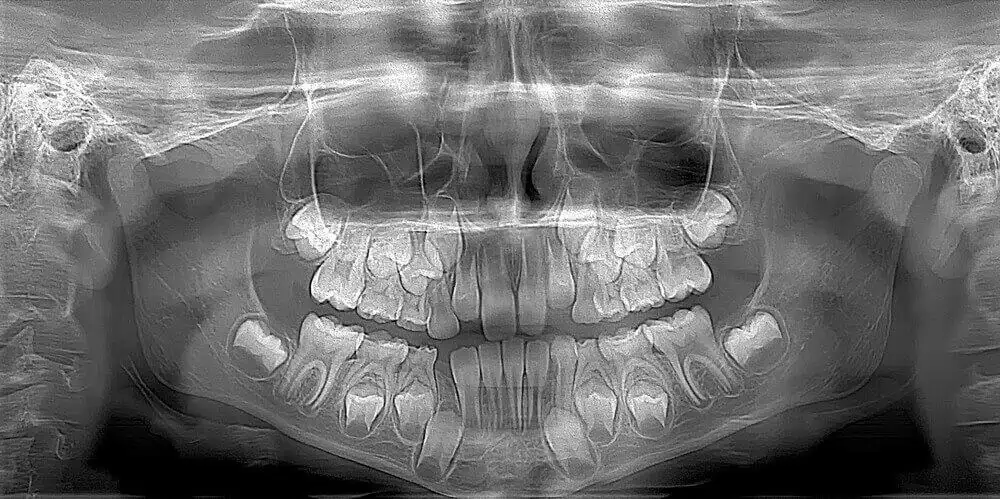

Baby Teeth Panoramic Xray. Recently in seattle, washington, a pediatric dentist was credited to saving a little girl’s life after she was losing an abnormal number of baby teeth at 4 years old. Image of the entire mouth including all teeth (including those that are not erupted yet), the upper and lower jaws, temporomandibular joints (tmj), nasal area, and sinuses. It is a two dimensional image that plays an important role in the examination and diagnostic process. Viewing development, position, and eruption of primary teeth so we can see all your child’s baby teeth and permanent teeth at one time3.

Image of the entire mouth including all teeth (including those that are not erupted yet), the upper and lower jaws, temporomandibular joints (tmj), nasal area, and sinuses. The jaw is a curved structure similar to that of a horseshoe. Taken at specific phases to monitor growth and development, identify extra and missing teeth, impacted teeth, as well as cysts and tumors. We usually take a panoramic xray when permanent teeth start to appear (approxiomately 6 yr. They are also used for planning orthodontic treatment and to evaluate growth and development. Although baby teeth are temporary, in order for healthy constants to form, they must be treated.

This particular type of digital image will show your orthodontist the following before starting you with braces. Image of the entire mouth including all teeth (including those that are not erupted yet), the upper and lower jaws, temporomandibular joints (tmj), nasal area, and sinuses. Taken at specific phases to monitor growth and development, identify extra and missing teeth, impacted teeth, as well as cysts and tumors. In teens and young adults we can monitor wisdom teeth. Viewing development, position, and eruption of primary teeth so we can see all your child’s baby teeth and permanent teeth at one time3.

Fractures of the teeth and/or jaws can be seen when it is difficult to open your mouth2. It is a two dimensional image that plays an important role in the examination and diagnostic process. It can show the placement of emerged teeth, emerging and impacted teeth within the same image. In teens and young adults we can monitor wisdom teeth. Taken at specific phases to monitor growth and development, identify extra and missing teeth, impacted teeth, as well as cysts and tumors.